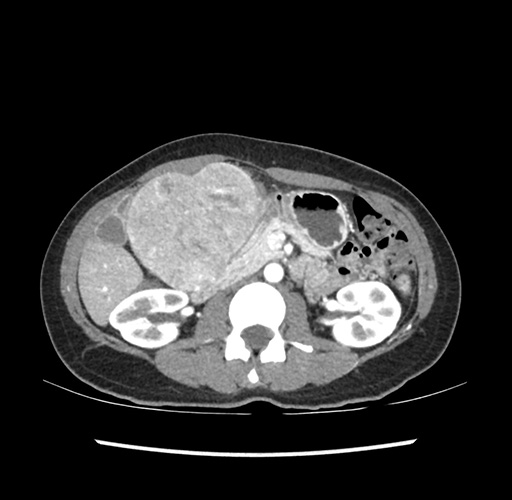

Imaging Analysis

Look through the patient's CT scan to identify any areas of concern for the necessary procedure.

Based on your CT findings, which issue(s) would give reason for "planned slowing down moment(s)" in this case?

Considering a standard left lateral sectionectomy procedure, what step(s) of the operation would you do differently in this case ?